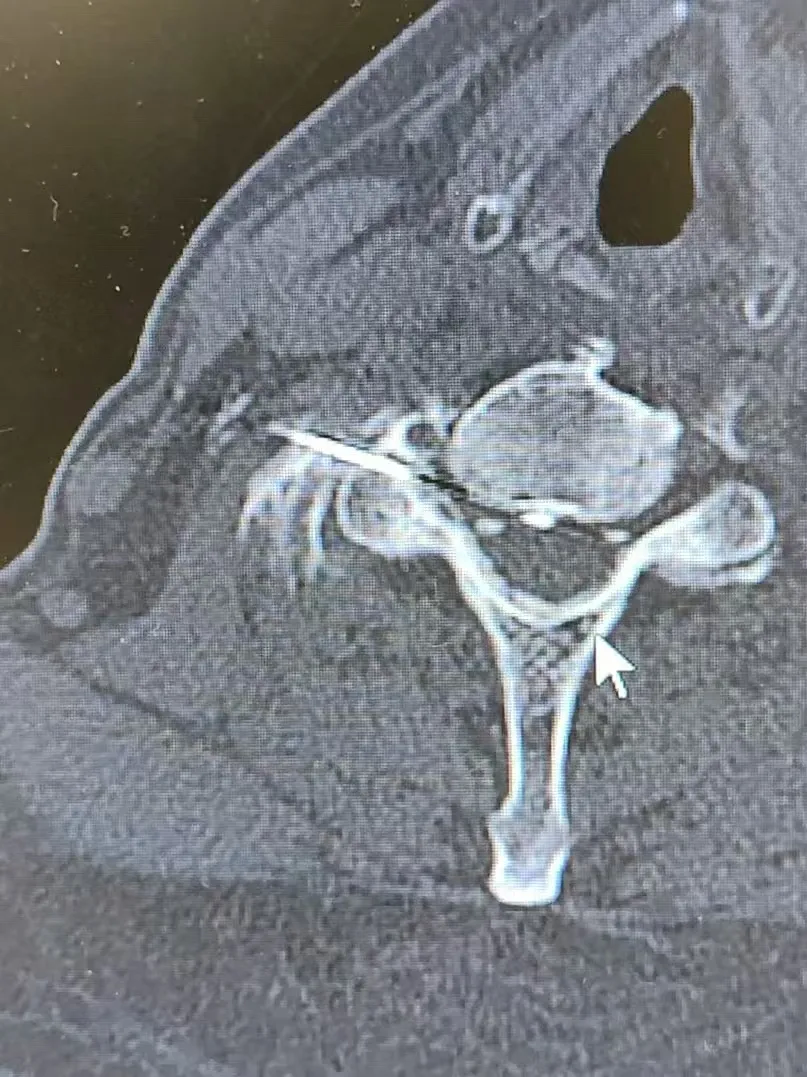

在CT引导下行神经根脉冲射频术

图片

CT引导下颈神经根脉冲射频术(左图),三叉神经半月结脉冲射频术(右图)